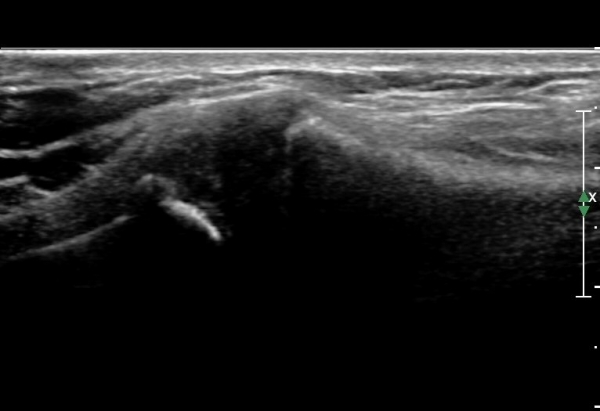

¿ìÃø Èä°ñ¼â°ñ°üÀýÃÊÀ½ÆÄ°Ë»ç¿¡¼­ °üÀýÀÇ ÅðÇ༭ º¯È­°¡ °üÂûµÊ(»çÁø 3, 4).